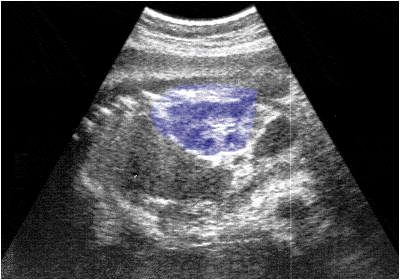

Ecografía de la región abdomino-pélvica de un feto de 20 semanas que muestra la imagen del rińón (azul).